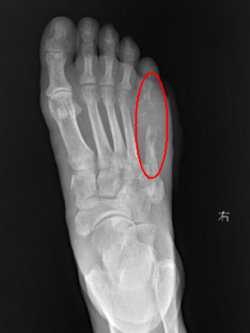

▲ 骨质破坏区

王颖博士为老张实施的对穿引流、冲洗创面直至无脓液渗出,并给予抗感染治疗。术前检查显示,老张的右足第5趾跖骨骨质均破坏,合并骨髓炎,并存在下肢动脉硬化、糖尿病的情况。